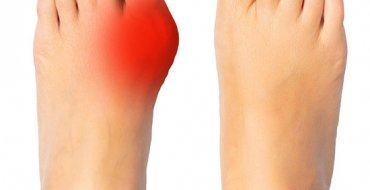

Підвищення рівня сечової кислоти: шляхи вирішення проблеми